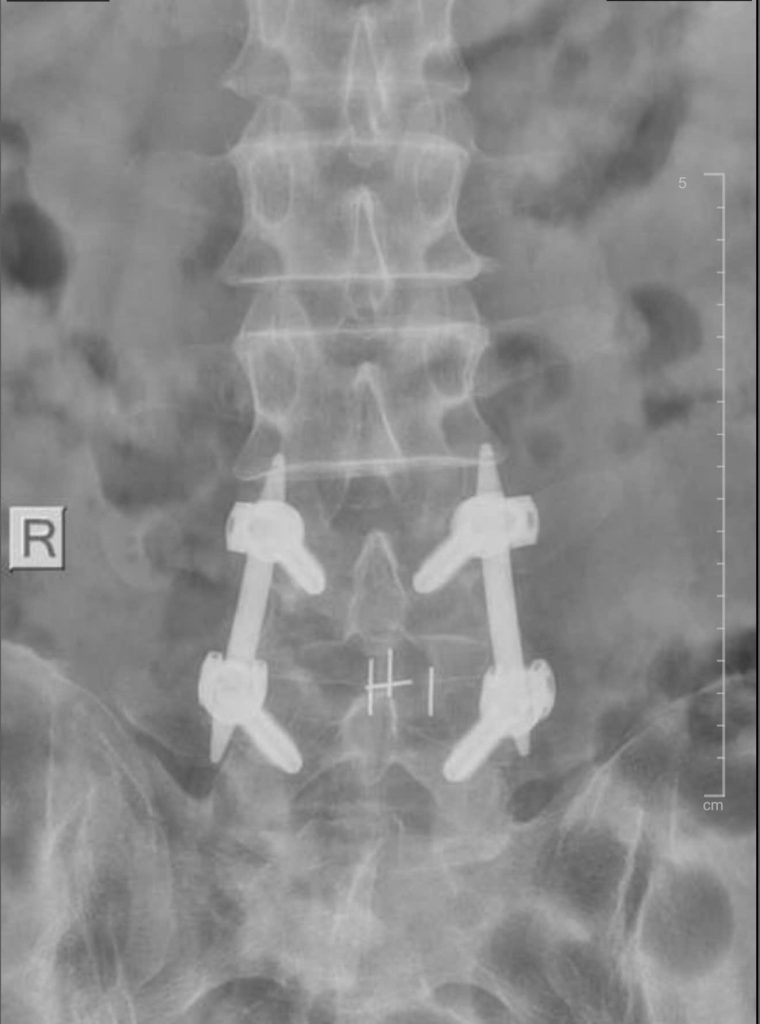

Đến khám tại Bệnh viện Đa khoa Xuyên Á Vĩnh Long, bệnh nhân được các bác sĩ khoa Ngoại Thần Kinh thăm khám kỹ lưỡng và chỉ định các cận lâm sàng cần thiết. Kết quả chụp cộng hưởng từ (MRI) 1.5 Tesla cho thấy bệnh nhân bị thoát vị đĩa đệm đốt sống thắt lưng L4 –> L5, chèn ép đường đi của rễ thần kinh hai bên.

Hình ảnh MRI của bệnh nhân thực hiện bắt vít qua da. Ảnh BV

Theo các bác sĩ, việc phẫu thuật để điều trị là rất cần thiết. Tuy vậy, bệnh nhân vô cùng lo lắng và phân vân. Trong trường hợp này, các bác sĩ tư vấn áp dụng phương pháp bắt vít qua da để điều trị, thay vì phải mổ hở. Với sự giải thích tận tình của các bác sĩ, bệnh nhân và gia đình yên tâm đồng ý phẫu thuật.

Hiện có phương pháp điều trị tiên tiến là bắt vít qua da (Percutaneous Pedicle Screw Fixation - PPSF), là kỹ thuật phẫu thuật ít xâm lấn để điều trị thoát vị đĩa đệm, gãy/trượt cột sống, giúp cố định cột sống hiệu quả bằng cách đặt vít qua các lỗ nhỏ dưới da, thay vì mổ mở rộng, nhờ đó giảm đau, giảm tổn thương mô mềm, rút ngắn thời gian nằm viện và phục hồi nhanh chóng, cho phép vận động sớm sau mổ.